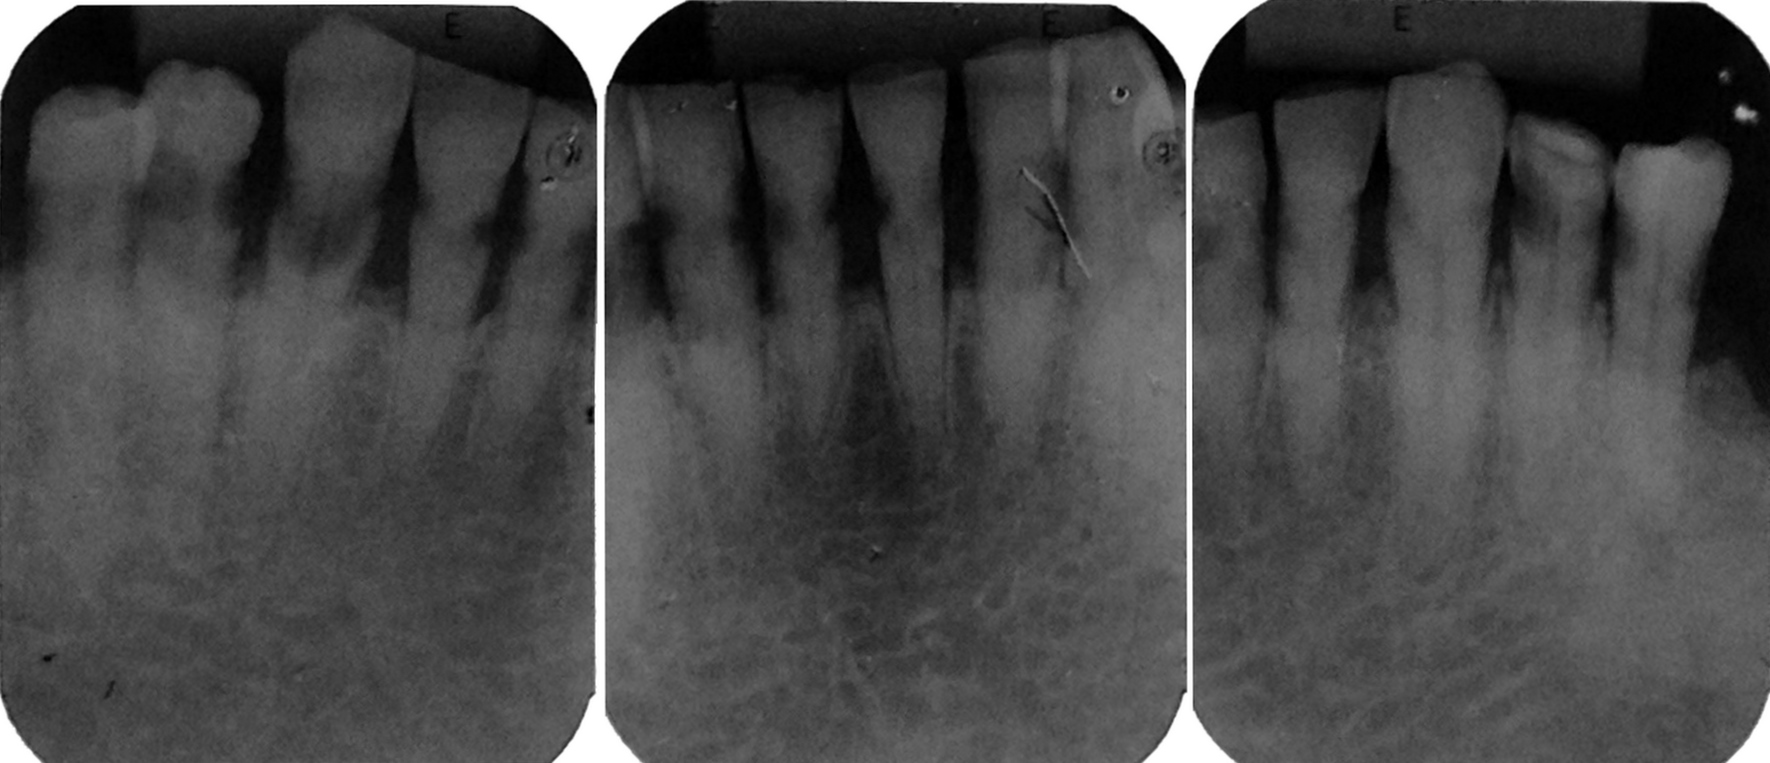

Osteoradionecrosis (ORN) is one of the most severe oral complications after the head and neck cancer treatment. Tooth extraction, through its traumatic stimulation, is identified as an important predisposing factor. Indications and preventive methods for carrying out these procedures in irradiated patients are questioned, thus, establishing appropriate protocols is essential. This article reports a case of multiple tooth extractions in a cancer patient whose preventive measures were taken without the occurrence of complications. Based on a literature review, this paper accounts the appropriate indications of this procedure, the risk of developing osteoradionecrosis, and the prevention possibilities for this sequela. In addition, this report addresses a viable oral rehabilitation alternative after this kind of surgery by using overdenture on the lower jaw teeth.